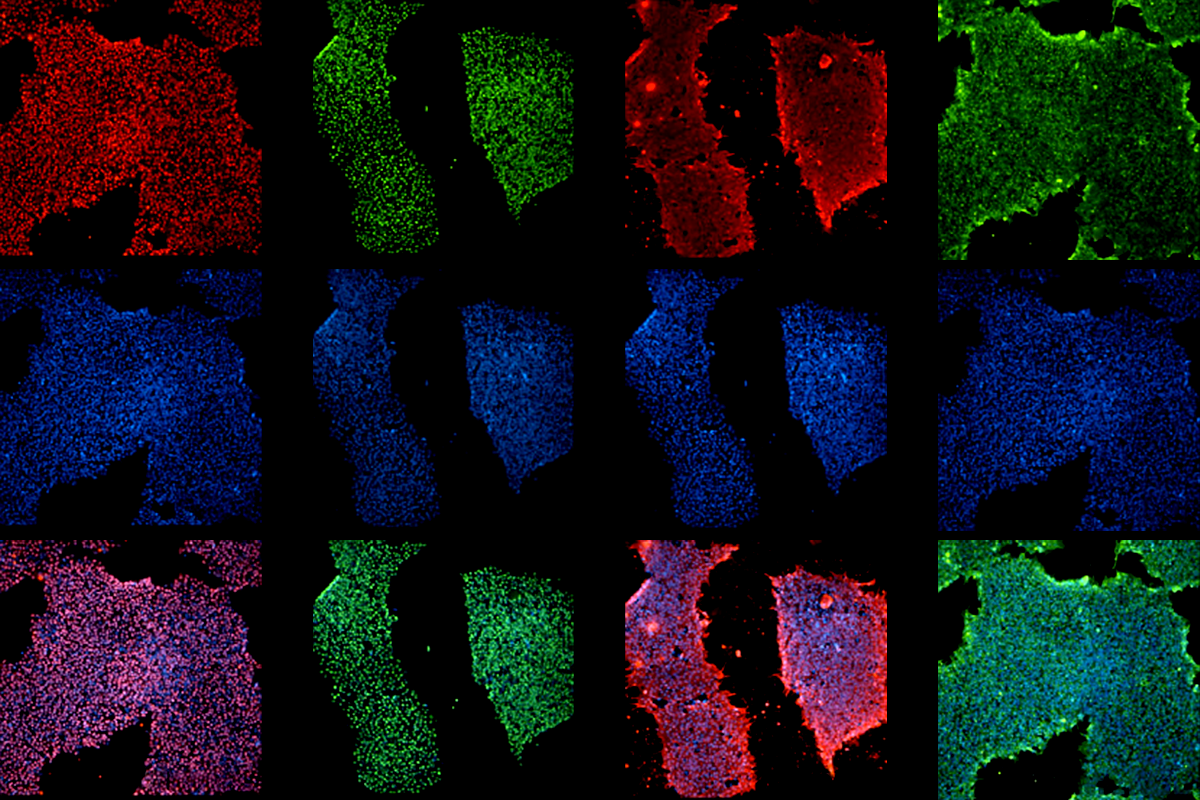

So far, the team has established 11 iPSC lines from local donors without Alzheimer’s disease, representing five ethnic groups in the region. One of the initiative’s projects involves introducing genetic variants associated with frontotemporal dementia or Alzheimer’s disease into the lines to study disease mechanisms in an African genetic background.